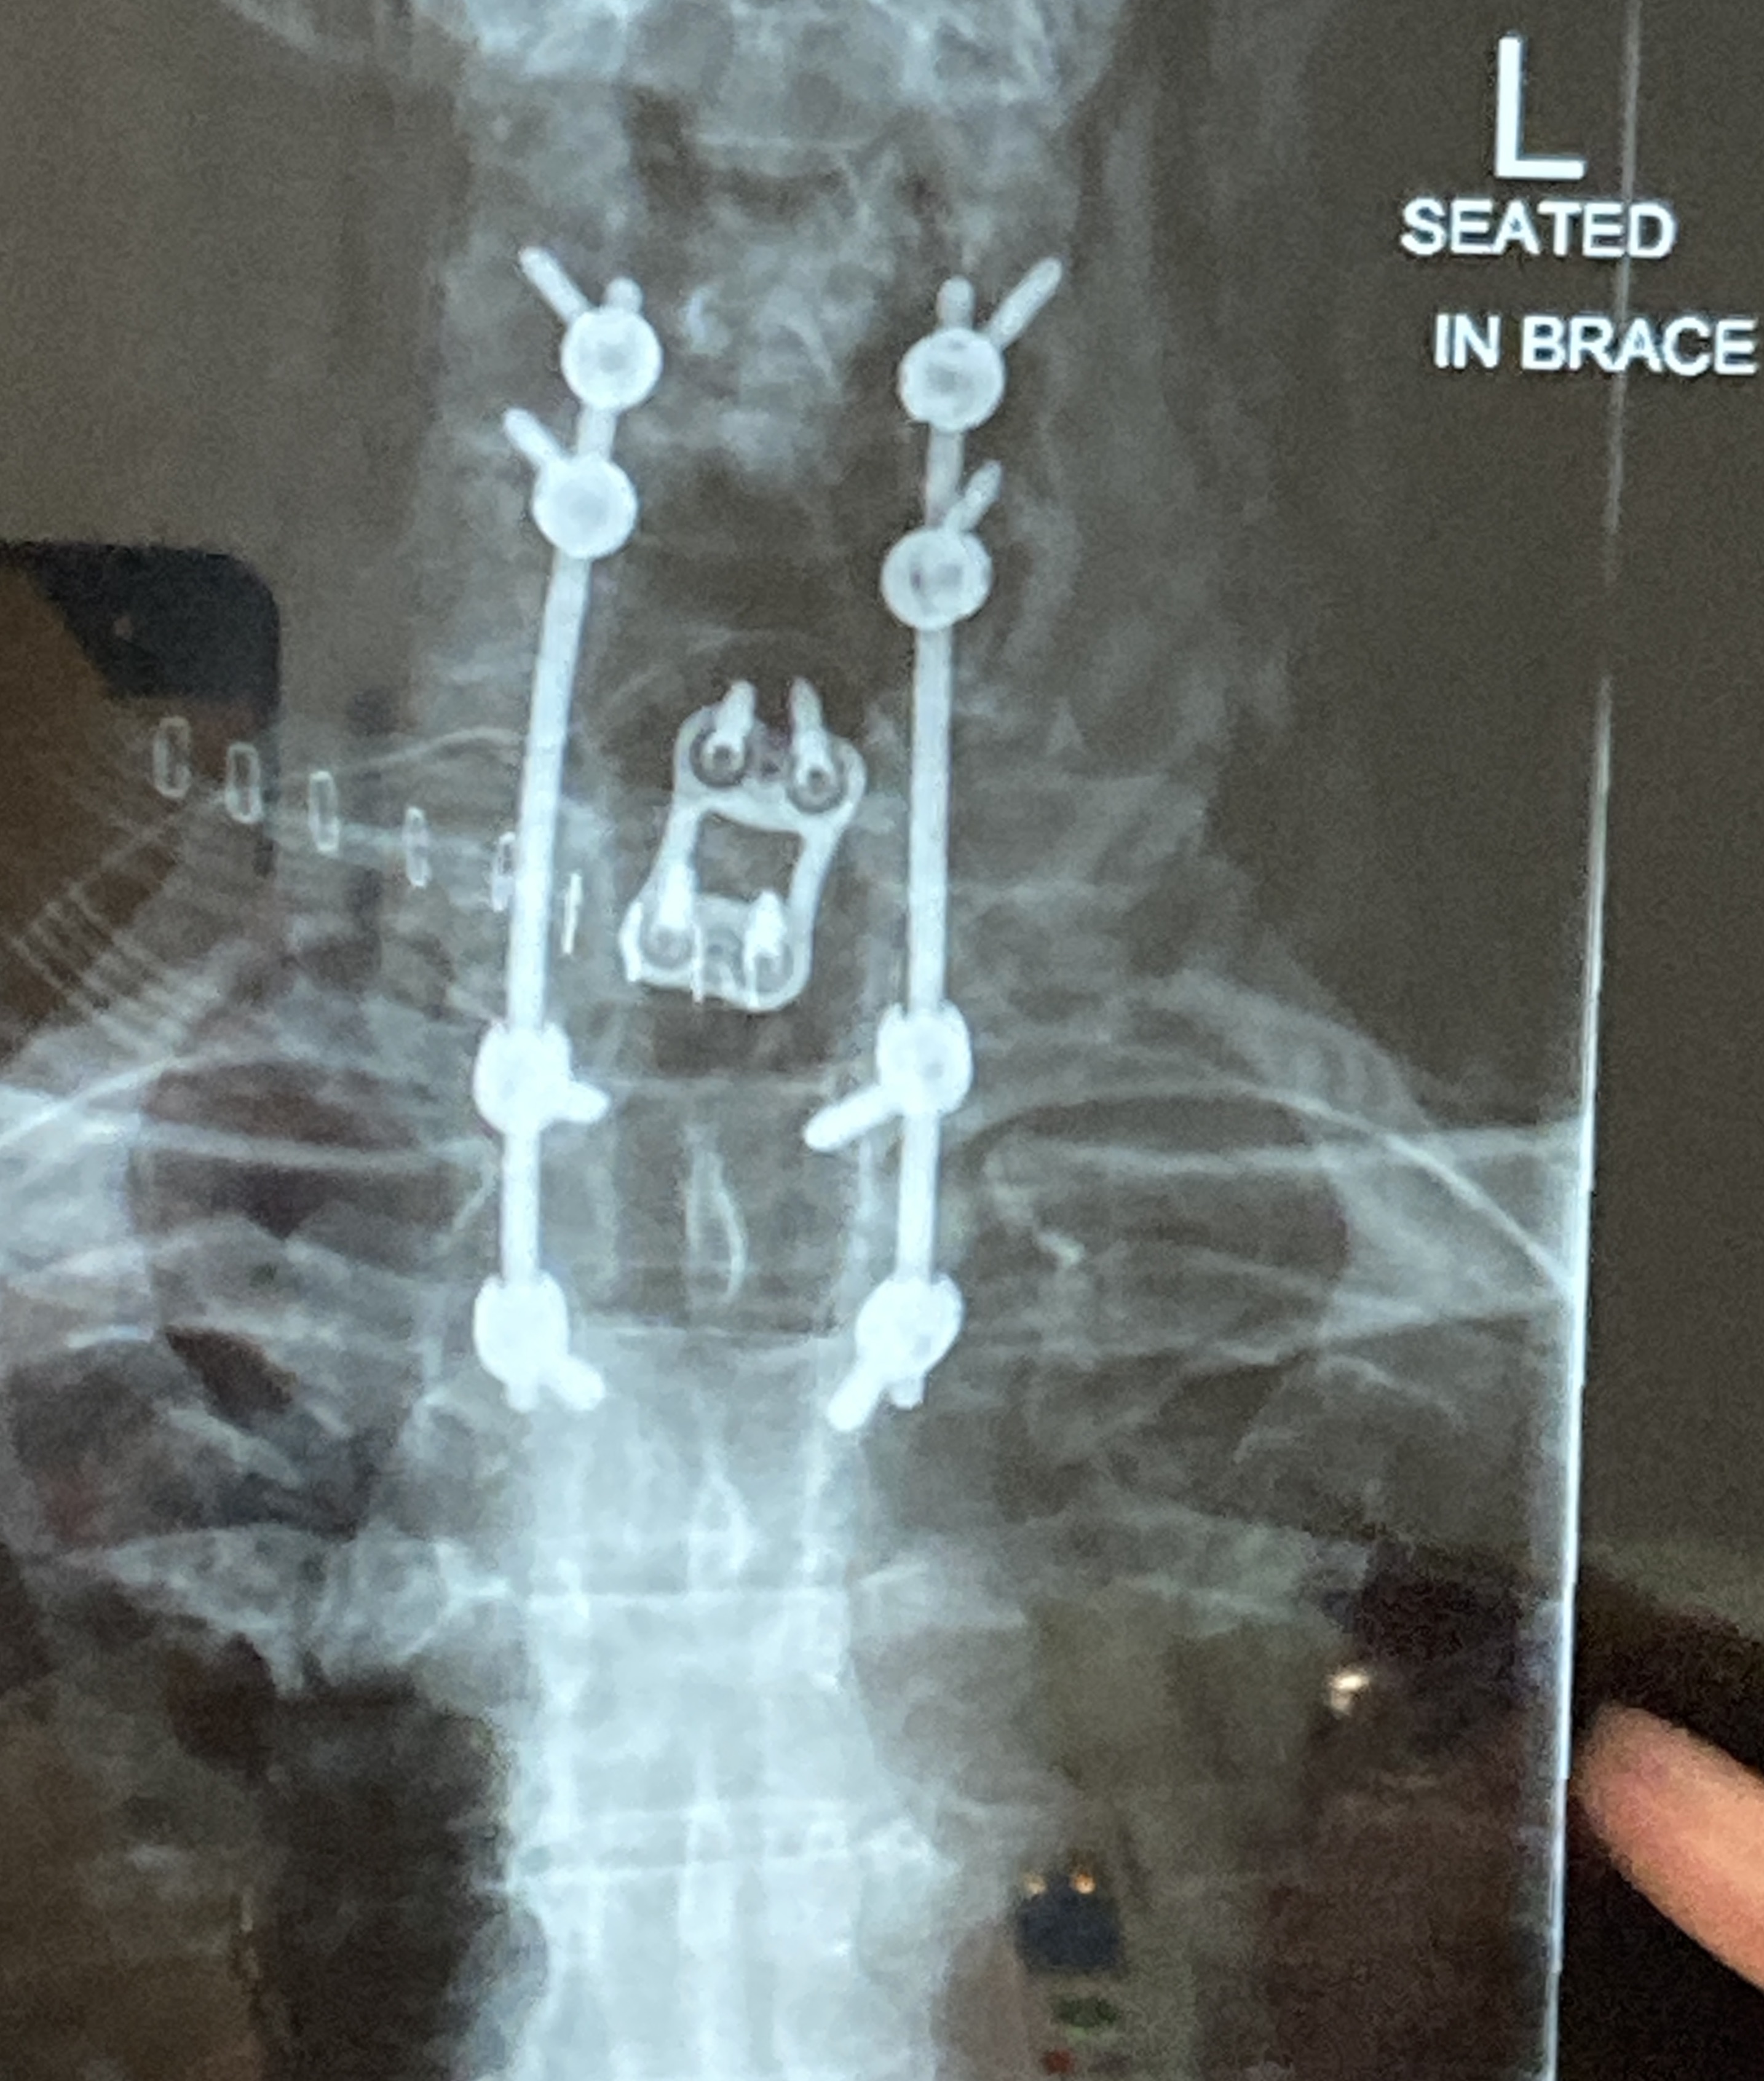

A few hours after the accident he underwent a 5 hour operation to relocate his neck, and to plate the 2 vertebrae that were dislocated. Then 3 days later, they went in again attaching rods to the undamaged vertebrae. His neck is quite bionic now! He’ll remain in a brace for at least 8 weeks, and then will be weaned off it slowly, while his neck muscles regain strength.